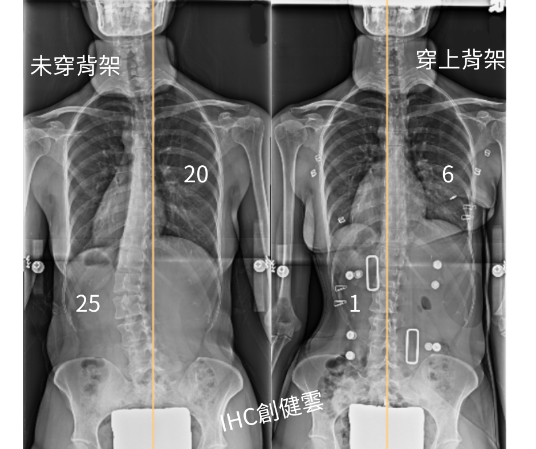

33歲脊椎側彎成年女性,胸彎20度,腰彎25度 穿上背架後立即矯正效果優異

33歲脊椎側彎女性,胸彎20度,腰彎25度,

穿上【施羅斯側彎矯治背架】後,胸彎6度,腰彎1度。

背架的立即矯正效果對成年人來說非常不錯~